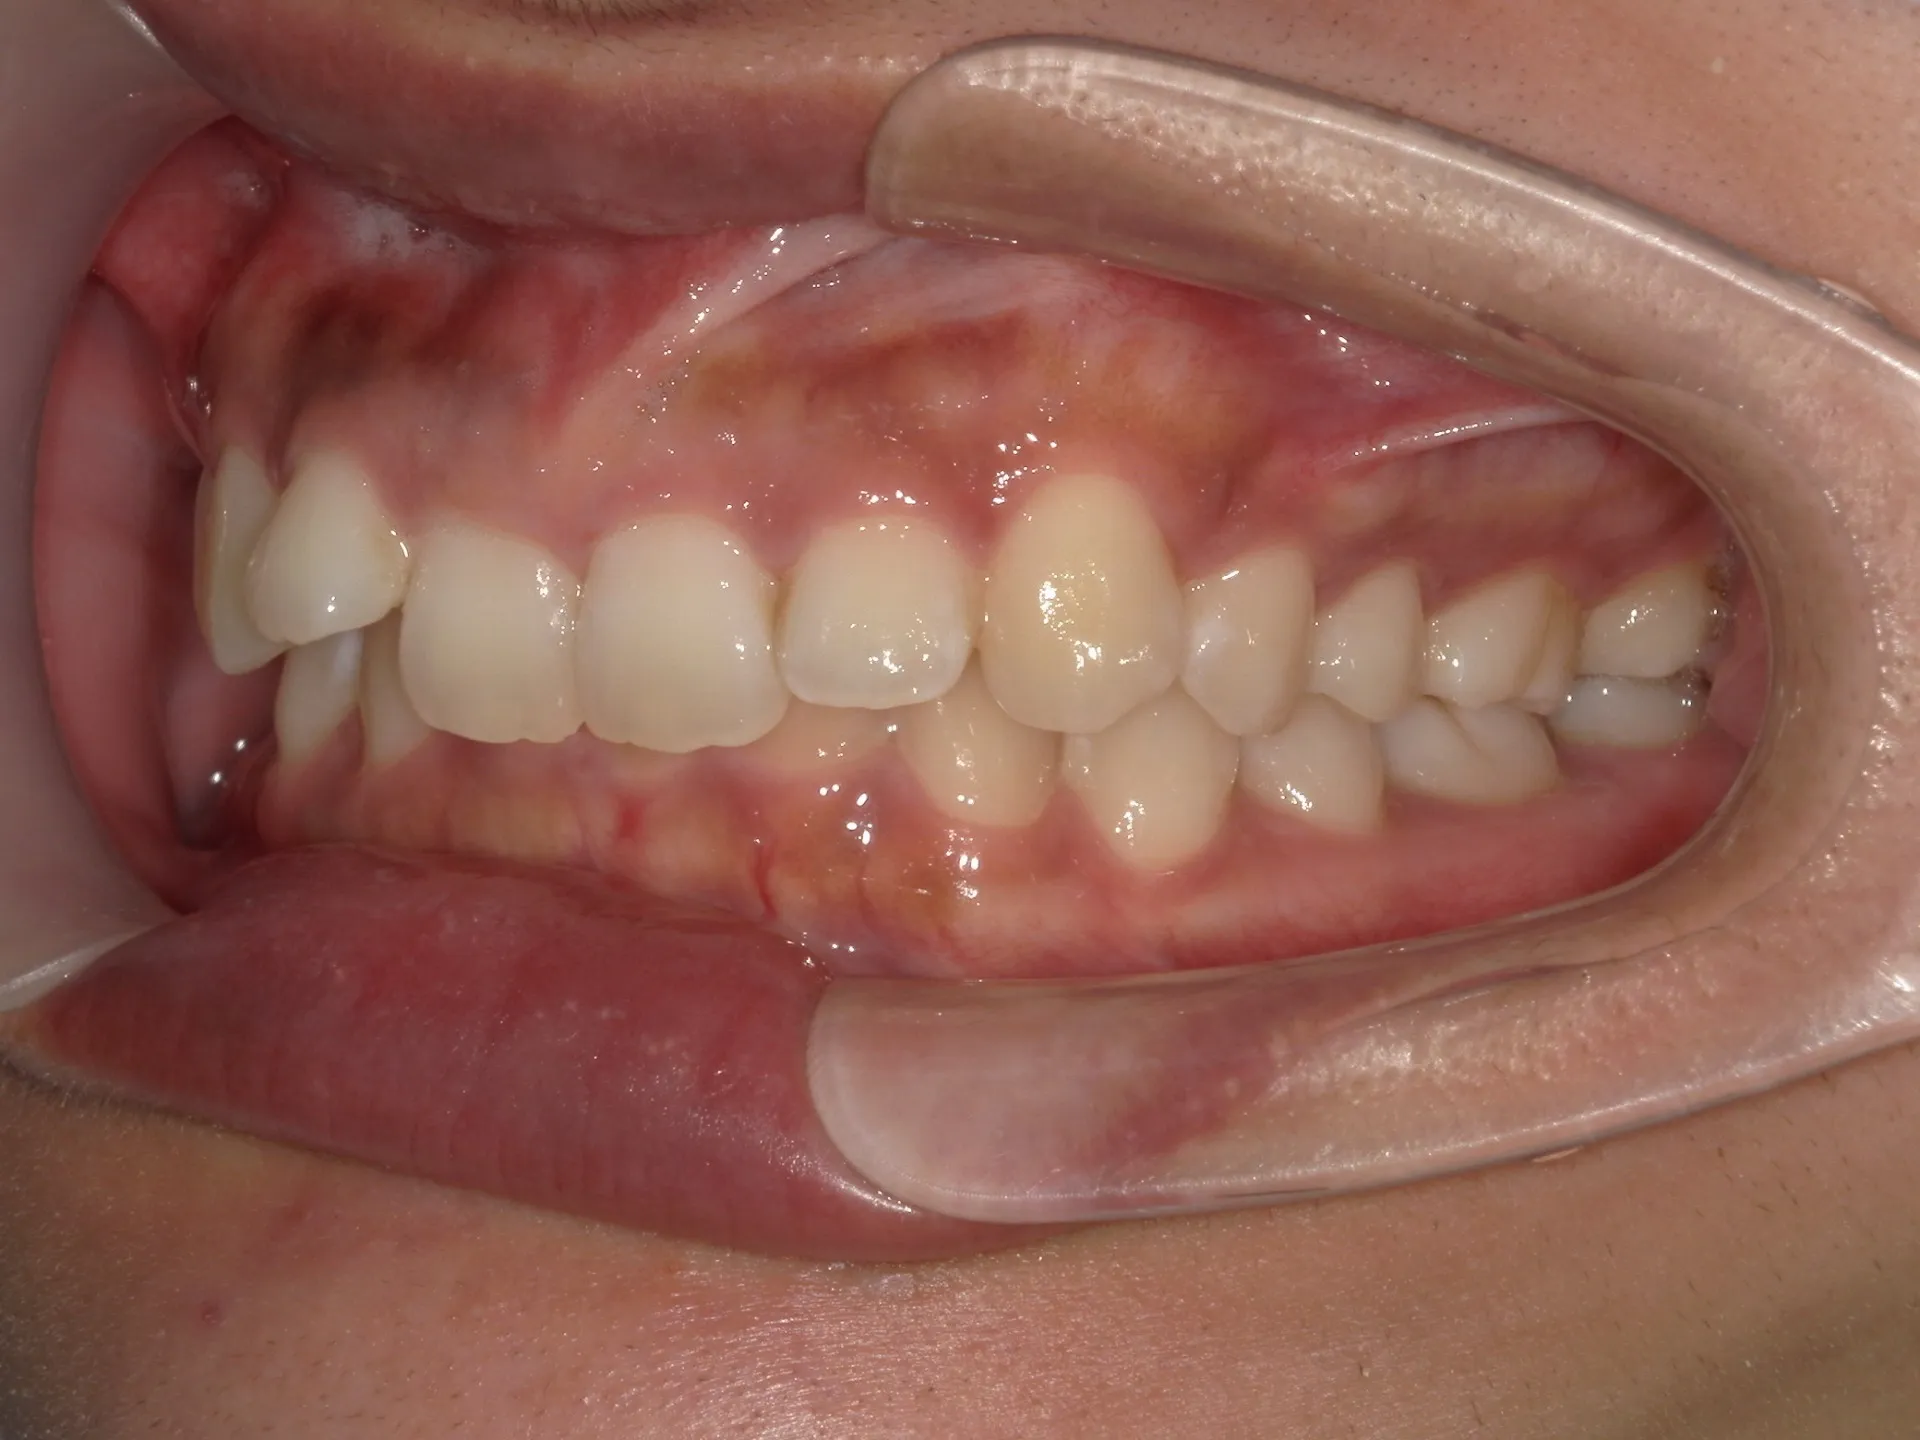

内側に倒れた前歯を矯正で正す!

前歯が内側に倒れてたりしませんか?

または2番目の歯が外側に飛び出していませんか?

この2つはよく同時に起こることがあります。

今回はインビザライン矯正治療(マウスピース矯正)で治療した症例についてご紹介いたします。